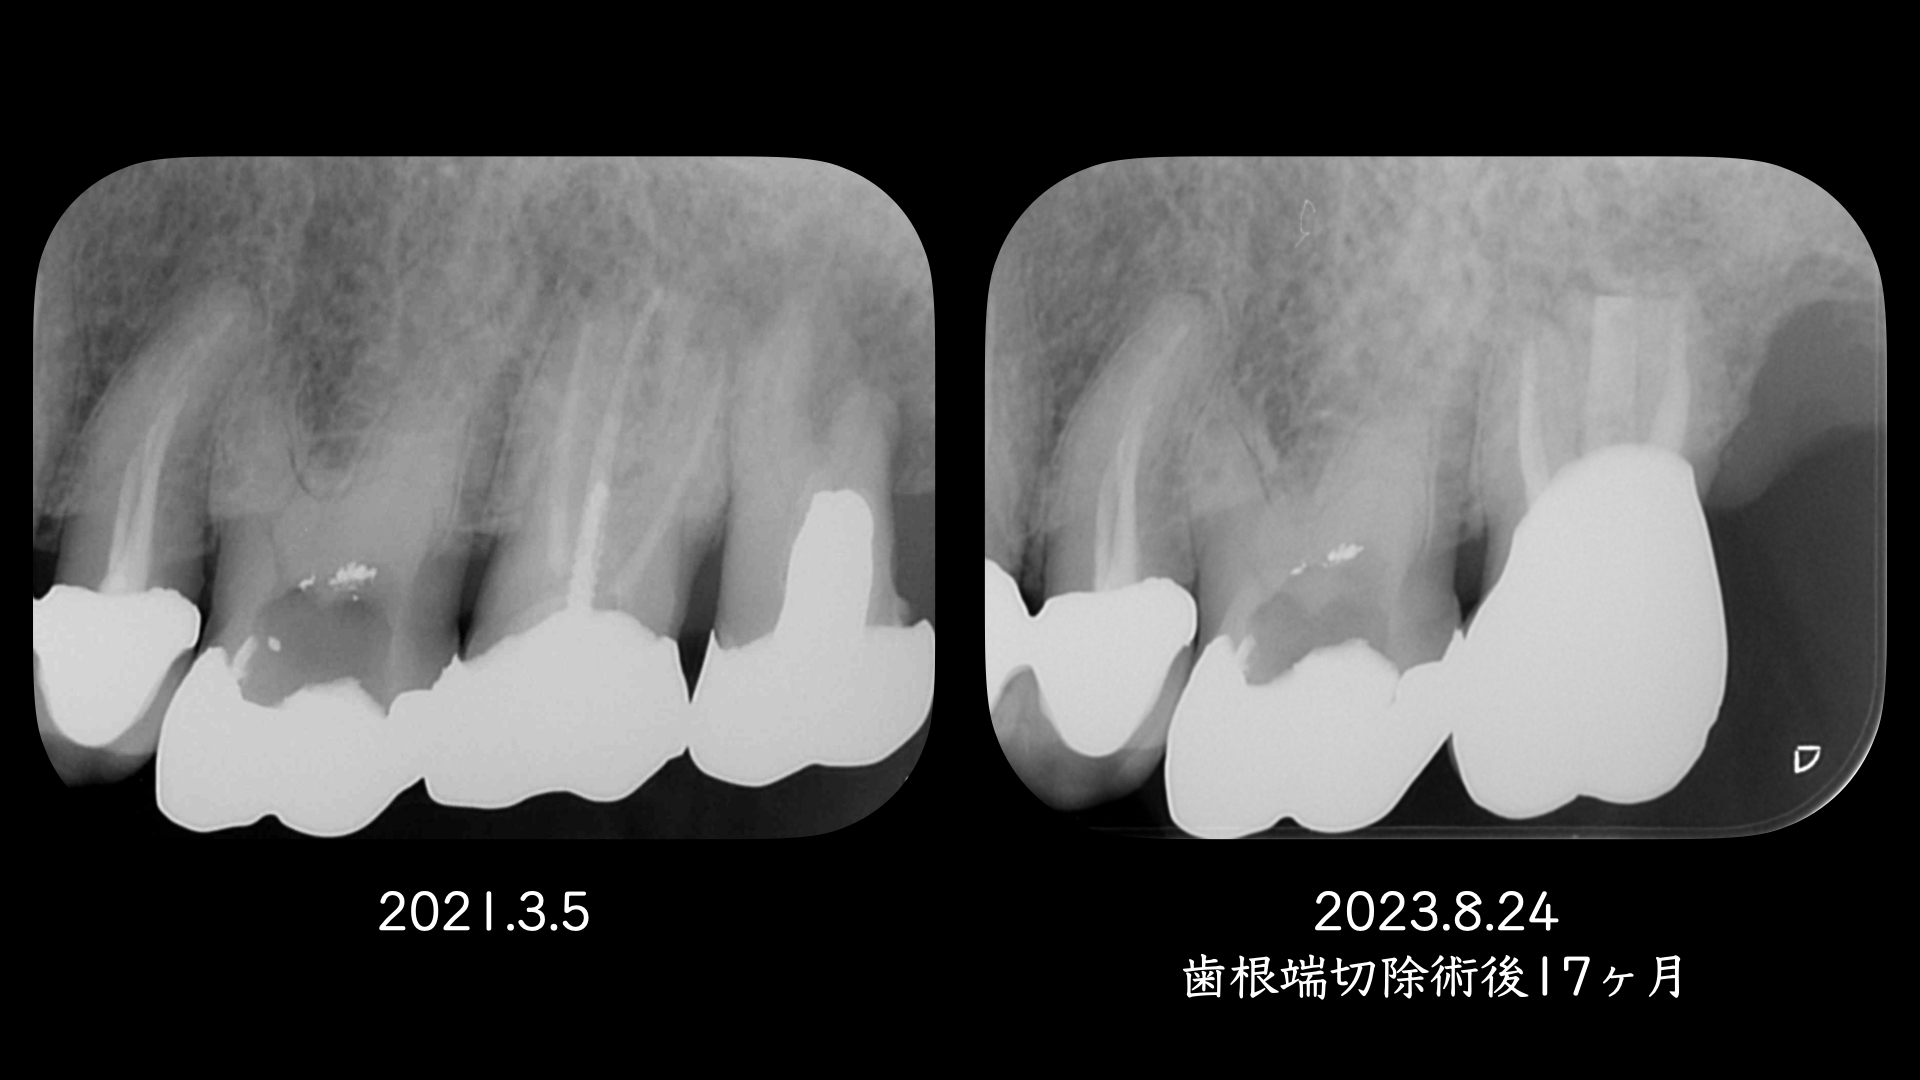

上顎口蓋根を歯根端切除(外科的歯内療法)した症例

右の画像のCT上で根尖部にかなり大きな透過像があります。

噛み合わせの反対側(下顎)はインプラント治療をおこなっており、経過をみていましたが全く変化がありませんでした。

患者さんの都合もあり1年後に歯根端切除(外科的歯内療法)をおこなうことになりました。

術後、歯根は骨に囲まれるように治癒にしました。